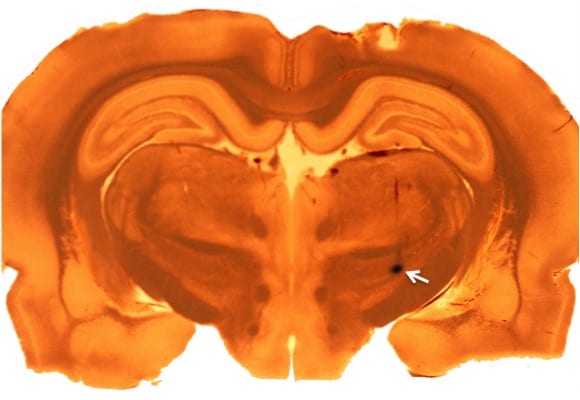

At the end of recording, pontamine sky-blue dye was iontophoretically injected into the recording site (white arrow) to confirm recording from the STN.